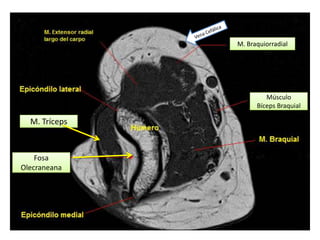

CORTES AXIALES

Vena Cefálica

M. Braquiorradial

M. Ancóneo

M. Braquial

M. Pronador

Redondo

Músculo

Bíceps Braquial

Tendón del

Tríceps Braquial

M. Tríceps

Fosa

Olecraneana